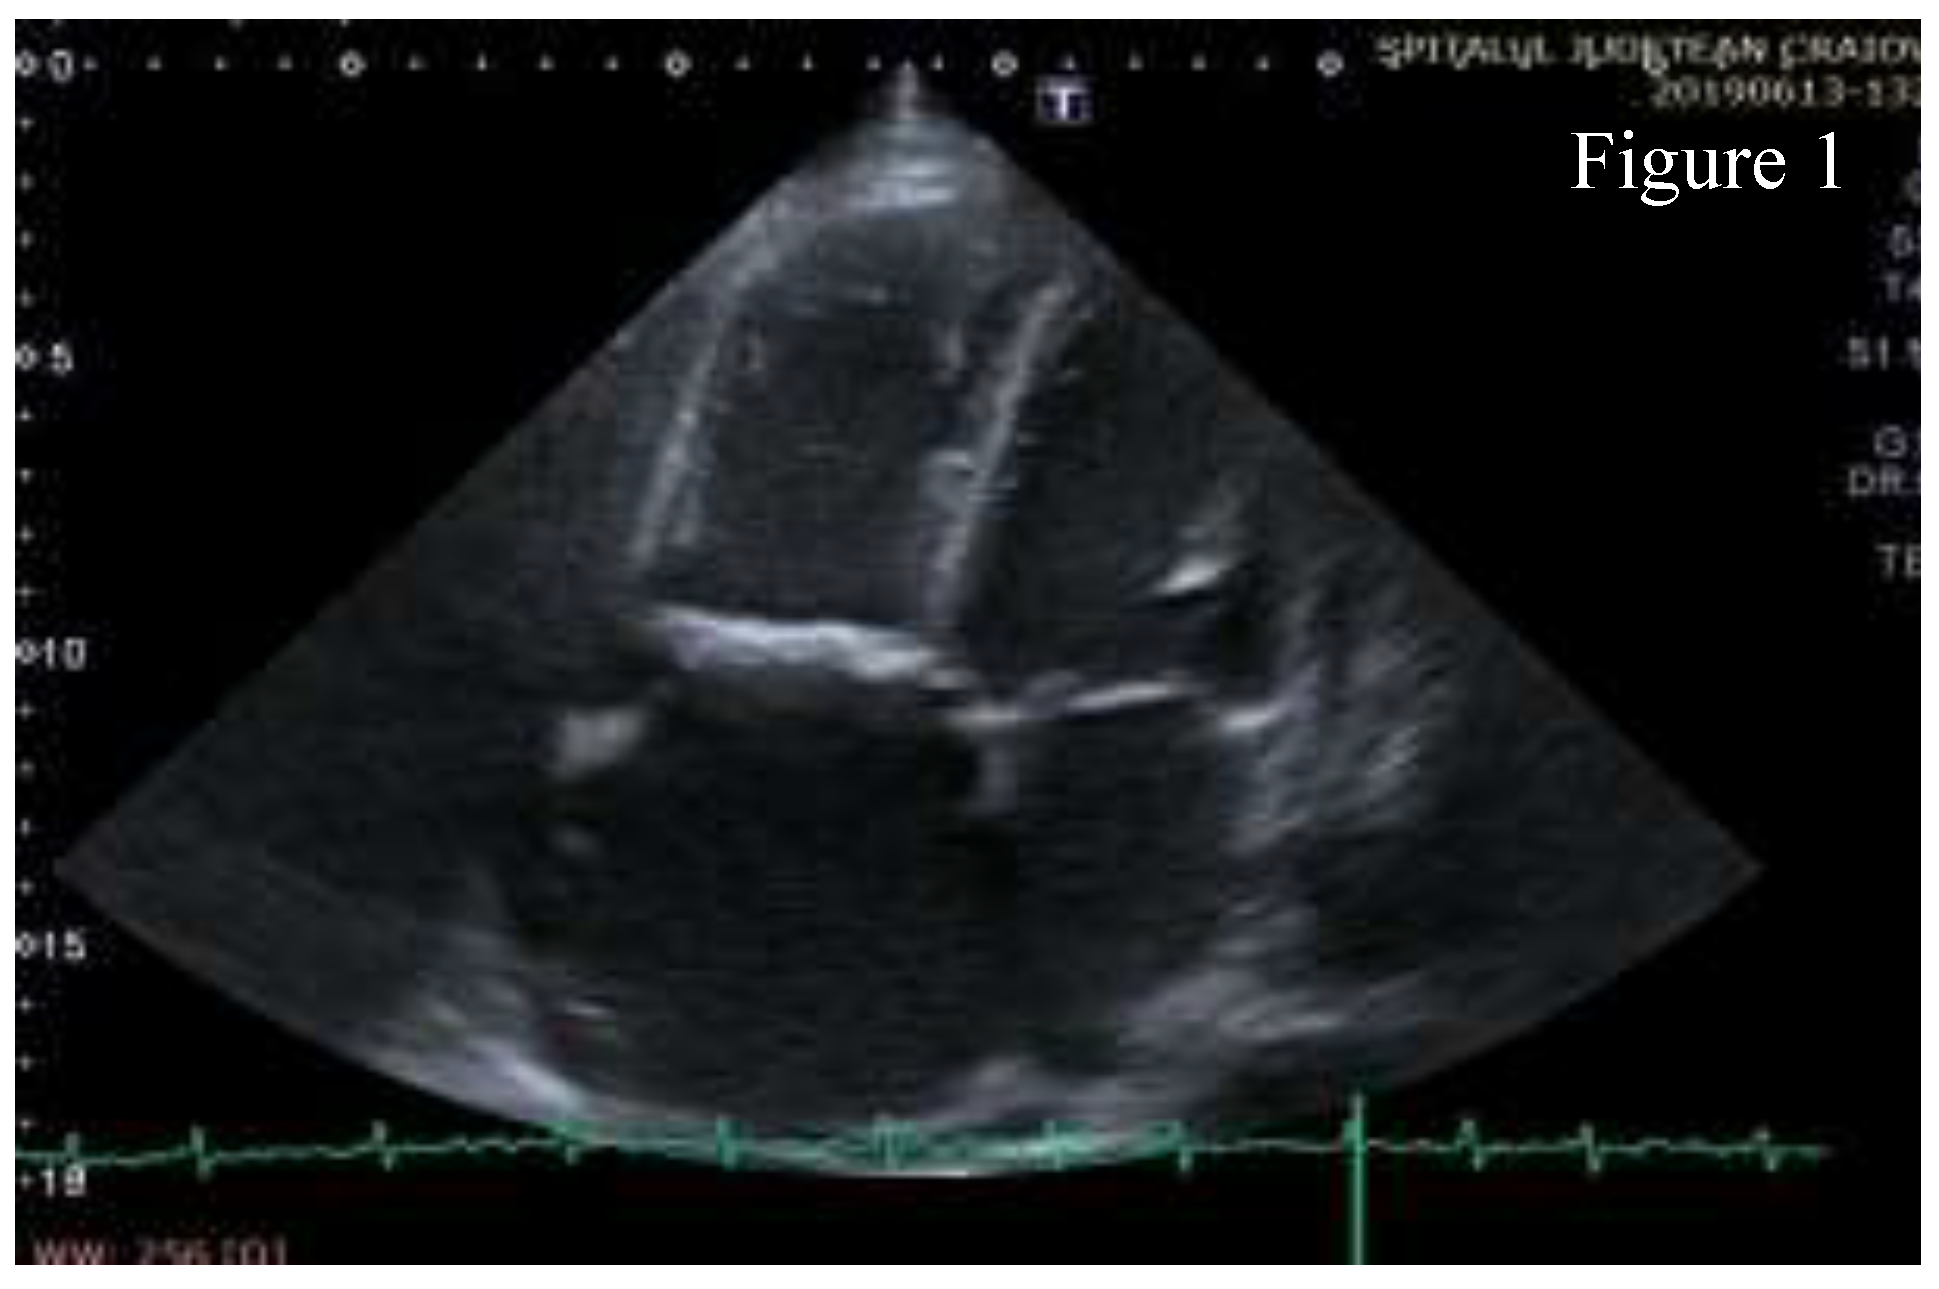

Transthoracic echocardiography (TTE) showed significant structural changes in the tricuspid valve. Anterior and posterior cusps were thickened, calcified, and had restricted motion. Subvalvular chords were thickened. Structural changes caused severe regurgitation (effective regurgitant orifice area= 0.57 cm2, regurgitant volume= 45 ml) and moderate stenosis (high diastolic gradient of 13/6 mmHg which contributed to the high inflow accompanying severe regurgitation). Right chambers were dilated with right ventricle longitudinal systolic dysfunction (TAPSE= 16mm, S’value = 10 cm/s) and with dilated inferior vena cava indicating increased pressure in the right atrium. These aspects are shown in Figure 1, Figure 2, Figure 3, Figure 4, Figure 5.

Figure 1.

Apical 4 chambers (A4C) view- thickened tricuspid valve leaflets and dilated right heart chambers.